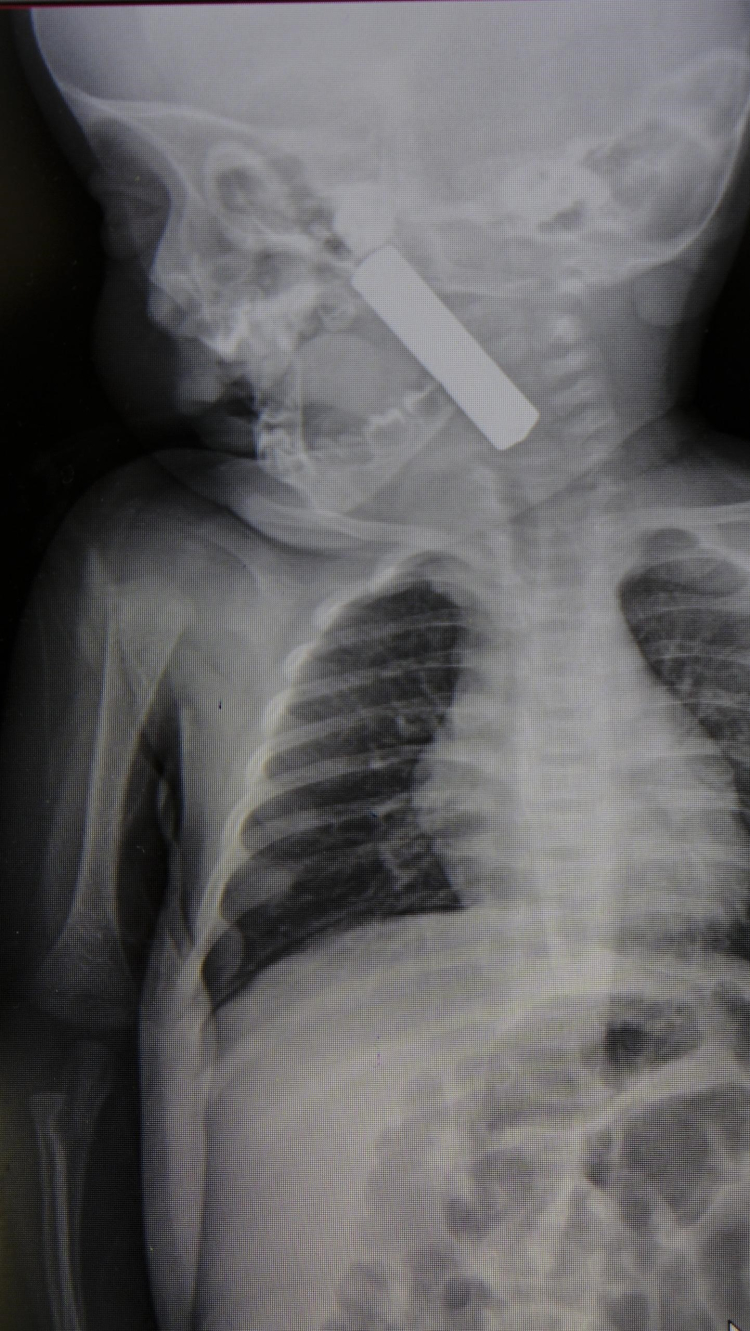

Edinilen bilgiye göre, Karaman’da yaşayan bir aile 6 aylık bebekleri E.A.’yı kusma ve nefes almada zorlanma şikayetiyle Karaman Eğitim ve Araştırma Hastanesi’ne getirdi. Acil serviste yapılan ilk müdahale ve tetkikler sonucunda, bebeğin boğazına yabancı bir cisim kaçtığı tespit edildi. Çekilen röntgen ve yapılan detaylı muayenede, boğazın alt kısmında kumanda pili olduğu ortaya çıktı.

Ameliyat sonrası açıklama yapan Doç. Dr. Uysal, şu bilgileri verdi: “Hastamızı gördüğümüzde siyanotik durumdaydı, yani morarmaya başlamıştı. Oksijen satürasyonu 90 civarındaydı. Röntgende ve muayenede, yemek borusunun üst kısmına kadar ilerlemiş bir kumanda pili tespit ettik. Hızla ameliyathaneye aldık. Ekibimizle birlikte, laringoskop ve özel aletlerle pili çıkardık. Müdahale sırasında ağız tabanında hasar oluşmuştu ama zamanında müdahale sayesinde bu hasar kalıcı olmadı. 24 saat boyunca gözlem altında tuttuk ve solunum sorunu kalmayınca bebeği taburcu ettik.”